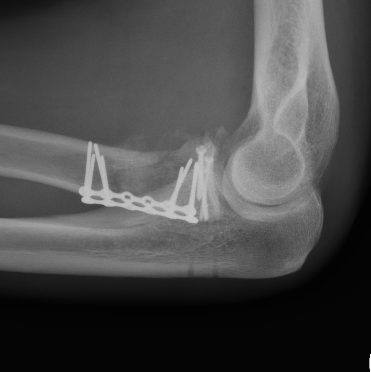

ORIF with plates

Lateral approach

- identify safe zone (90 degrees between radial styloid) and Lister's tubercle)

- lag articular surface first if required

- pre-contoured low profile plates

- distal limit is bicipital tuberosity

- check ROM intra-operatively

- plates often bulky and may limit ROM

- close annular ligament